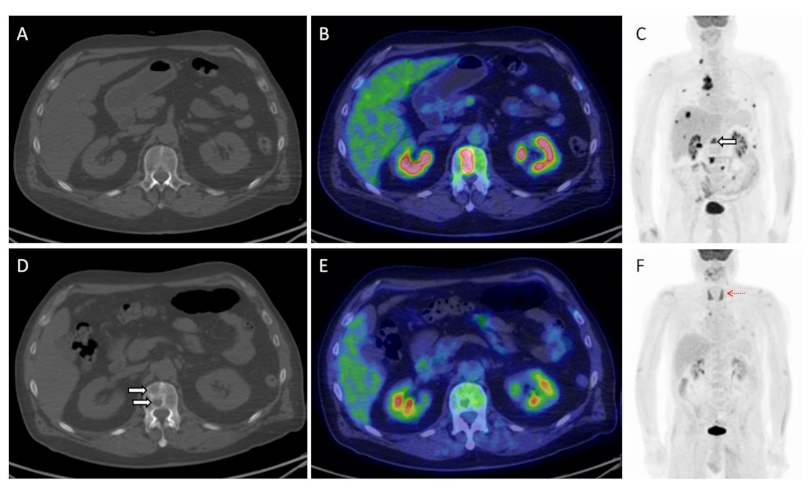

| Sachpekidis et al. | 2021 | retrospective | melanoma | 31 | ipilimumab, pembrolizumab, nivolumab plus ipilimumab | EORTC, PERCIMT, SLRmean, SLRmax | PET/CT, performed after two ICIs’ cycles, can identify the majority of non-responders | [61] |

| Sachpekidis et al. | 2021 | prospective | melanoma | 25 | nivolumab, pembrolizumab, nivolumab plus ipilimumab | SUVmean, SUVmax and quantitative on dynamic PET (K1, k3, influx, FD, fractal dimension) | SUVmean, SUVmax and FD adversely affected PFS | [62] |